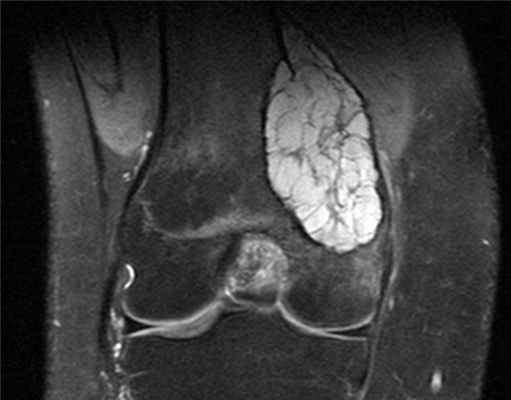

(Справа) МРТ, сагиттальная проекция, режим Т1: у этого же пациента визуализируются области высокоинтенсивного сигнала, соответствующие геморрагическому компоненту, окруженные низкоинтенсивной зоной. Визуализируются уровни жидкости. (Слева) МРТ, сагиттальная проекция, режим Т2 с подавлением сигнала от жира: уровни жидкости визуализируются гораздо более четко. Патологический очаг хорошо отграничен, однако объем непосредственного поражения бедренной кости больше, чем предполагалось после рентгенографии. Обратите внимание на отек костного мозга.

3. МРТ при аневризмальной костной кисте:

• Визуализируются перемычки

• Кисты с различной интенсивностью сигнала во всех последовательностях (различное состояние компонентов крови)

• Уровни жидкость-жидкость четче визуализируются в последовательностях, чувствительных к жидкости:

о Различная плотность геморрагического компонента

• Отсутствие контрастного усиления кистозных компонентов:

о Возможно контрастирование перемычек; по типу пчелиных сот

• Хорошо отграниченный очаг с тонким низкоинтенсивным склерозированным краем

• Отек окружающей кости и мягких тканей

о Внимательно анализируйте изображение для исключения проникающей опухоли, например телеангиэктатической остеосаркомы

• Большинство патологических очагов характеризуется дольчатыми зонами уровней жидкости, но бывают исключения: